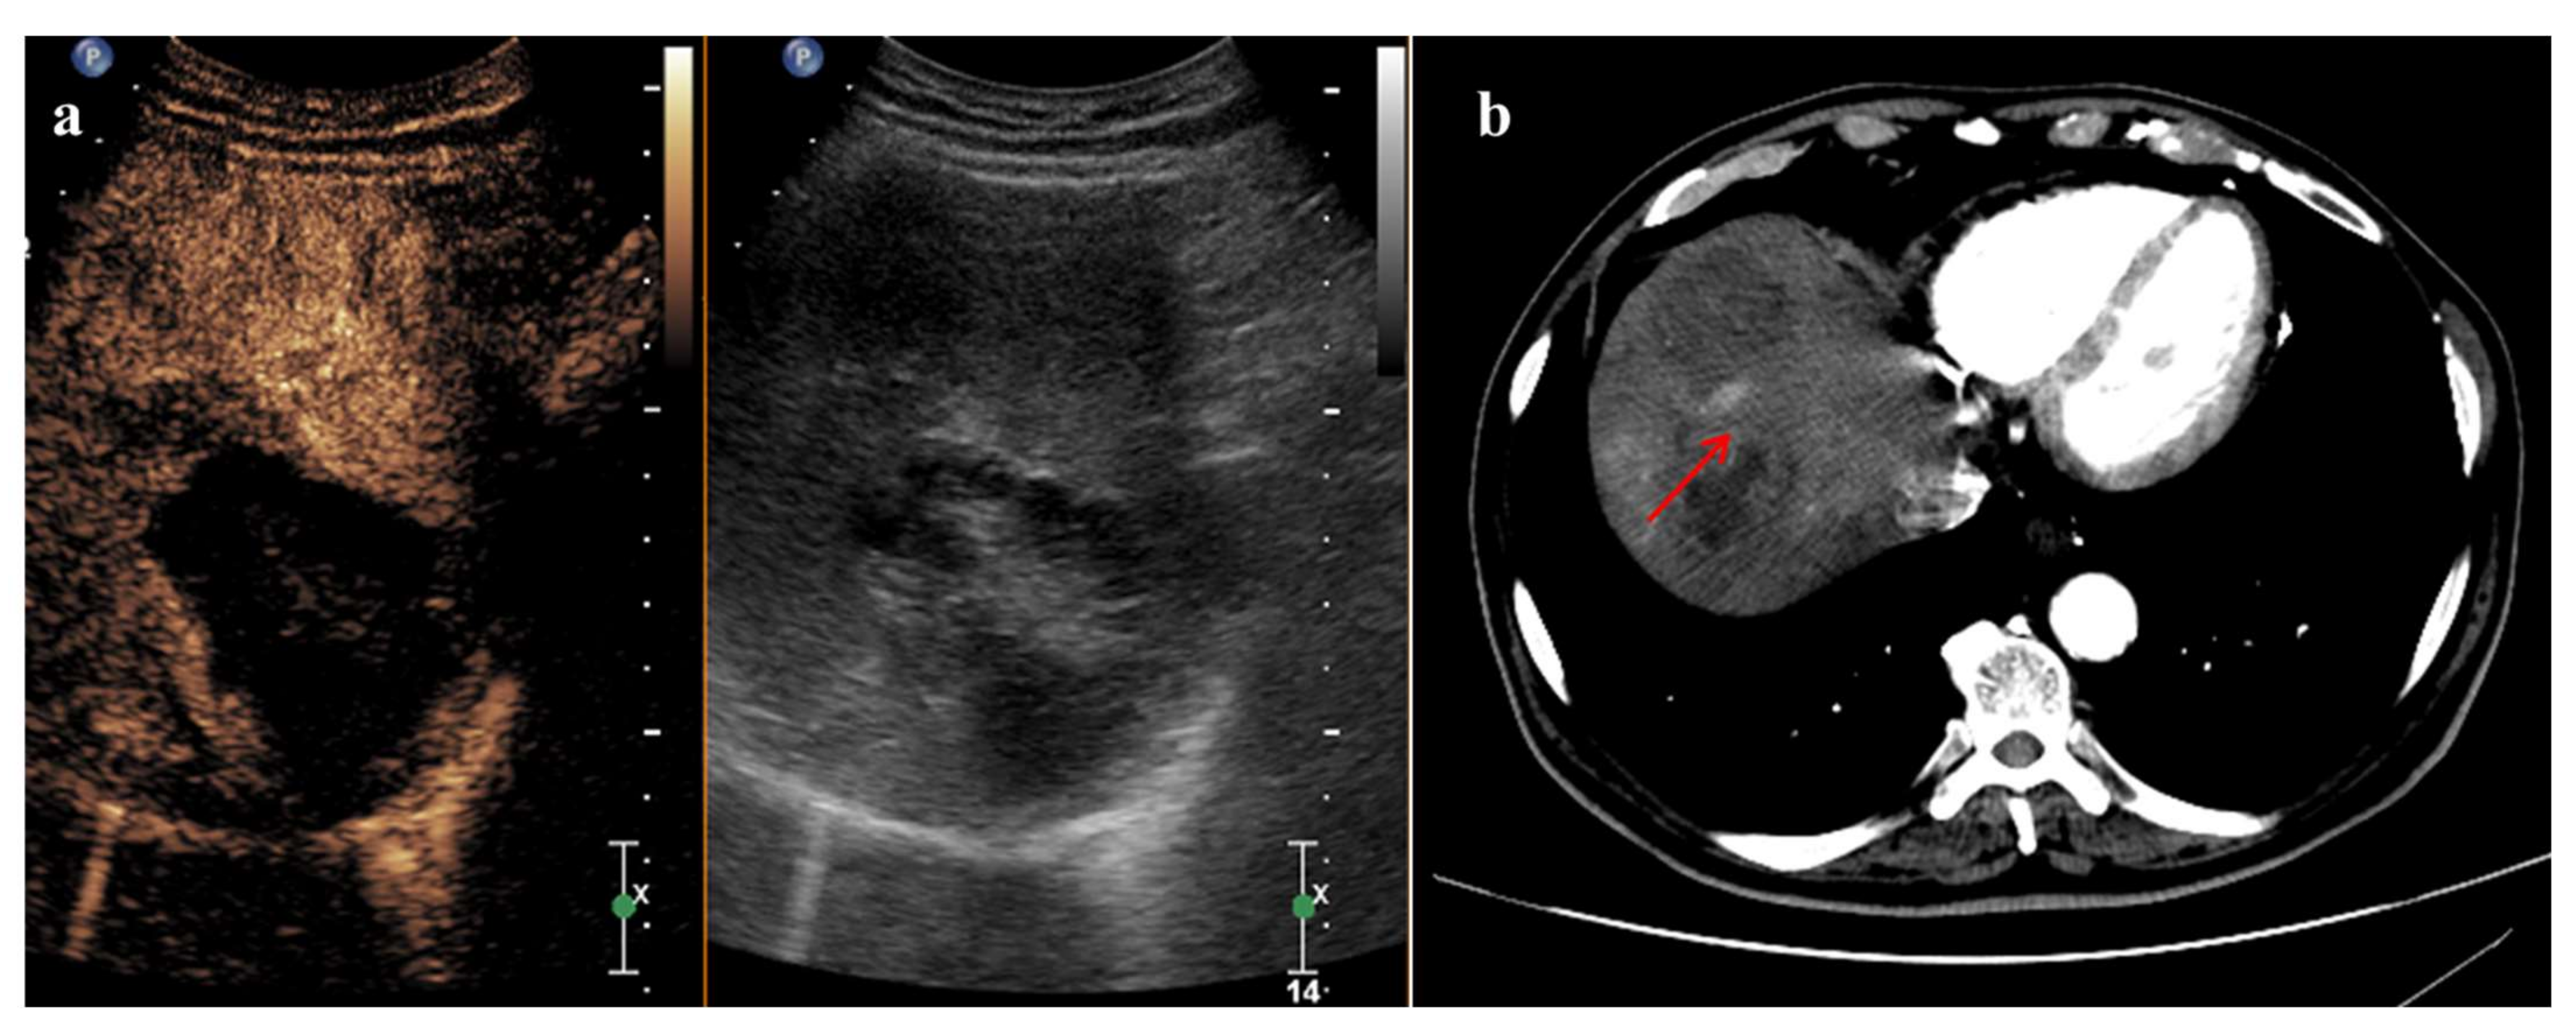

3. Radiofrequency Ablation and CEUS

- Ricci, P.; Cantisani, V.; Drudi, F.; Pagliara, E.; Bezzi, M.; Meloni, F.; Calliada, F.; Erturk, S.M.; D’Andrea, V.; D’Ambrosio, U.; et al. Is contrast-enhanced US alternative to spiral CT in the assessment of treatment outcome of radiofrequency ablation in hepatocellular carcinoma? Ultraschall Med. Eur. J. Ultrasound 2009, 30, 252–258. [Google Scholar] [CrossRef] [Green Version]

- Lu, M.D.; Yu, X.L.; Li, A.H.; Jiang, T.A.; Chen, M.H.; Zhao, B.Z.; Zhou, X.D.; Wang, J.R. Comparison of contrast enhanced ultrasound and contrast enhanced CT or MRI in monitoring percutaneous thermal ablation procedure in patients with hepatocellular carcinoma: A multi-center study in China. Ultrasound Med. Biol. 2007, 33, 1736–1749. [Google Scholar] [CrossRef] [PubMed]

- Zheng, S.G.; Xu, H.X.; Lu, M.D.; Xie, X.Y.; Xu, Z.F.; Liu, G.J.; Liu, L.N. Role of contrast-enhanced ultrasound in follow-up assessment after ablation for hepatocellular carcinoma. World J. Gastroenterol. 2013, 19, 855–865. [Google Scholar] [CrossRef]

- Leoni, S.; Piscaglia, F.; Granito, A.; Borghi, A.; Galassi, M.; Marinelli, S.; Terzi, E.; Bolondi, L. Characterization of primary and recurrent nodules in liver cirrhosis using contrast-enhanced ultrasound: Which vascular criteria should be adopted? Ultraschall Med. Eur. J. Ultrasound 2013, 34, 280–287. [Google Scholar] [CrossRef]

- Wu, J.Y.; Bai, X.M.; Wang, H.; Xu, Q.; Wang, S.; Wu, W.; Yan, K.; Yang, W. The Perfusion Features of Recurrent Hepatocellular Carcinoma After Radiofrequency Ablation Using Contrast-Enhanced Ultrasound and Pathological Stemness Evaluation: Compared to Initial Tumors. Front. Oncol. 2020, 10, 1464. [Google Scholar] [CrossRef]

- Han, X.; Dong, J.; Liu, Z.; Wu, B.; Tian, Y.; Tan, H.; Cheng, W. Quantitative dynamic contrast-enhanced ultrasound to predict intrahepatic recurrence of hepatocellular carcinoma after radiofrequency ablation: A cohort study. Int. J. Hyperth. 2020, 37, 1066–1073. [Google Scholar] [CrossRef]

- Gao, Y.; Zheng, D.Y.; Cui, Z.; Ma, Y.; Liu, Y.Z.; Zhang, W. Predictive value of quantitative contrast-enhanced ultrasound in hepatocellular carcinoma recurrence after ablation. World J. Gastroenterol. 2015, 21, 10418–10426. [Google Scholar] [CrossRef]

- Maruyama, H.; Takahashi, M.; Shimada, T.; Sekimoto, T.; Kamesaki, H.; Kanai, F.; Yokosuka, O. Pretreatment microbubble-induced enhancement in hepatocellular carcinoma predicts intrahepatic distant recurrence after radiofrequency ablation. Am. J. Roentgenol. 2013, 200, 570–577. [Google Scholar] [CrossRef]